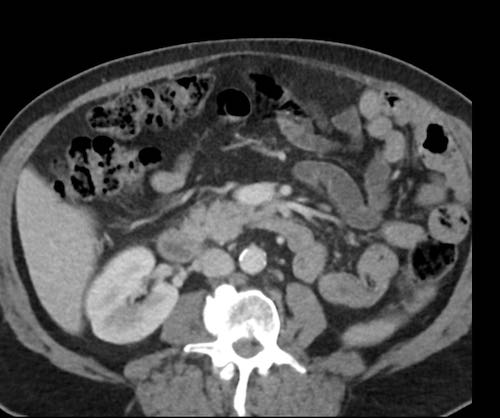

Ca lâm sàng 2

Cuộn qua các lát cắt.

Bạn có thể phát hiện tất cả các tổn thương cấy ghép phúc mạc không?